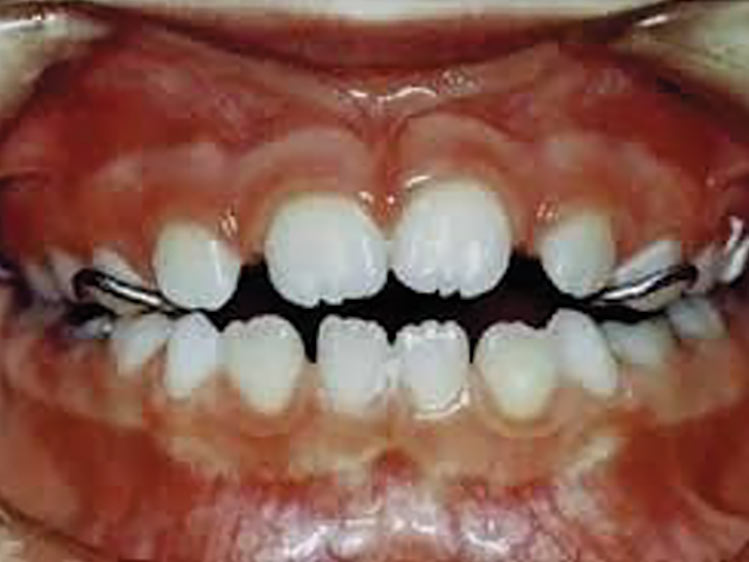

Porque dentes apinhados acumulam mais alimentos, mais placa bacteriana, mais tártaro, mais inflamação de gengiva, sangramento, mau hálito e aumentando o risco de surgimento de cáries.